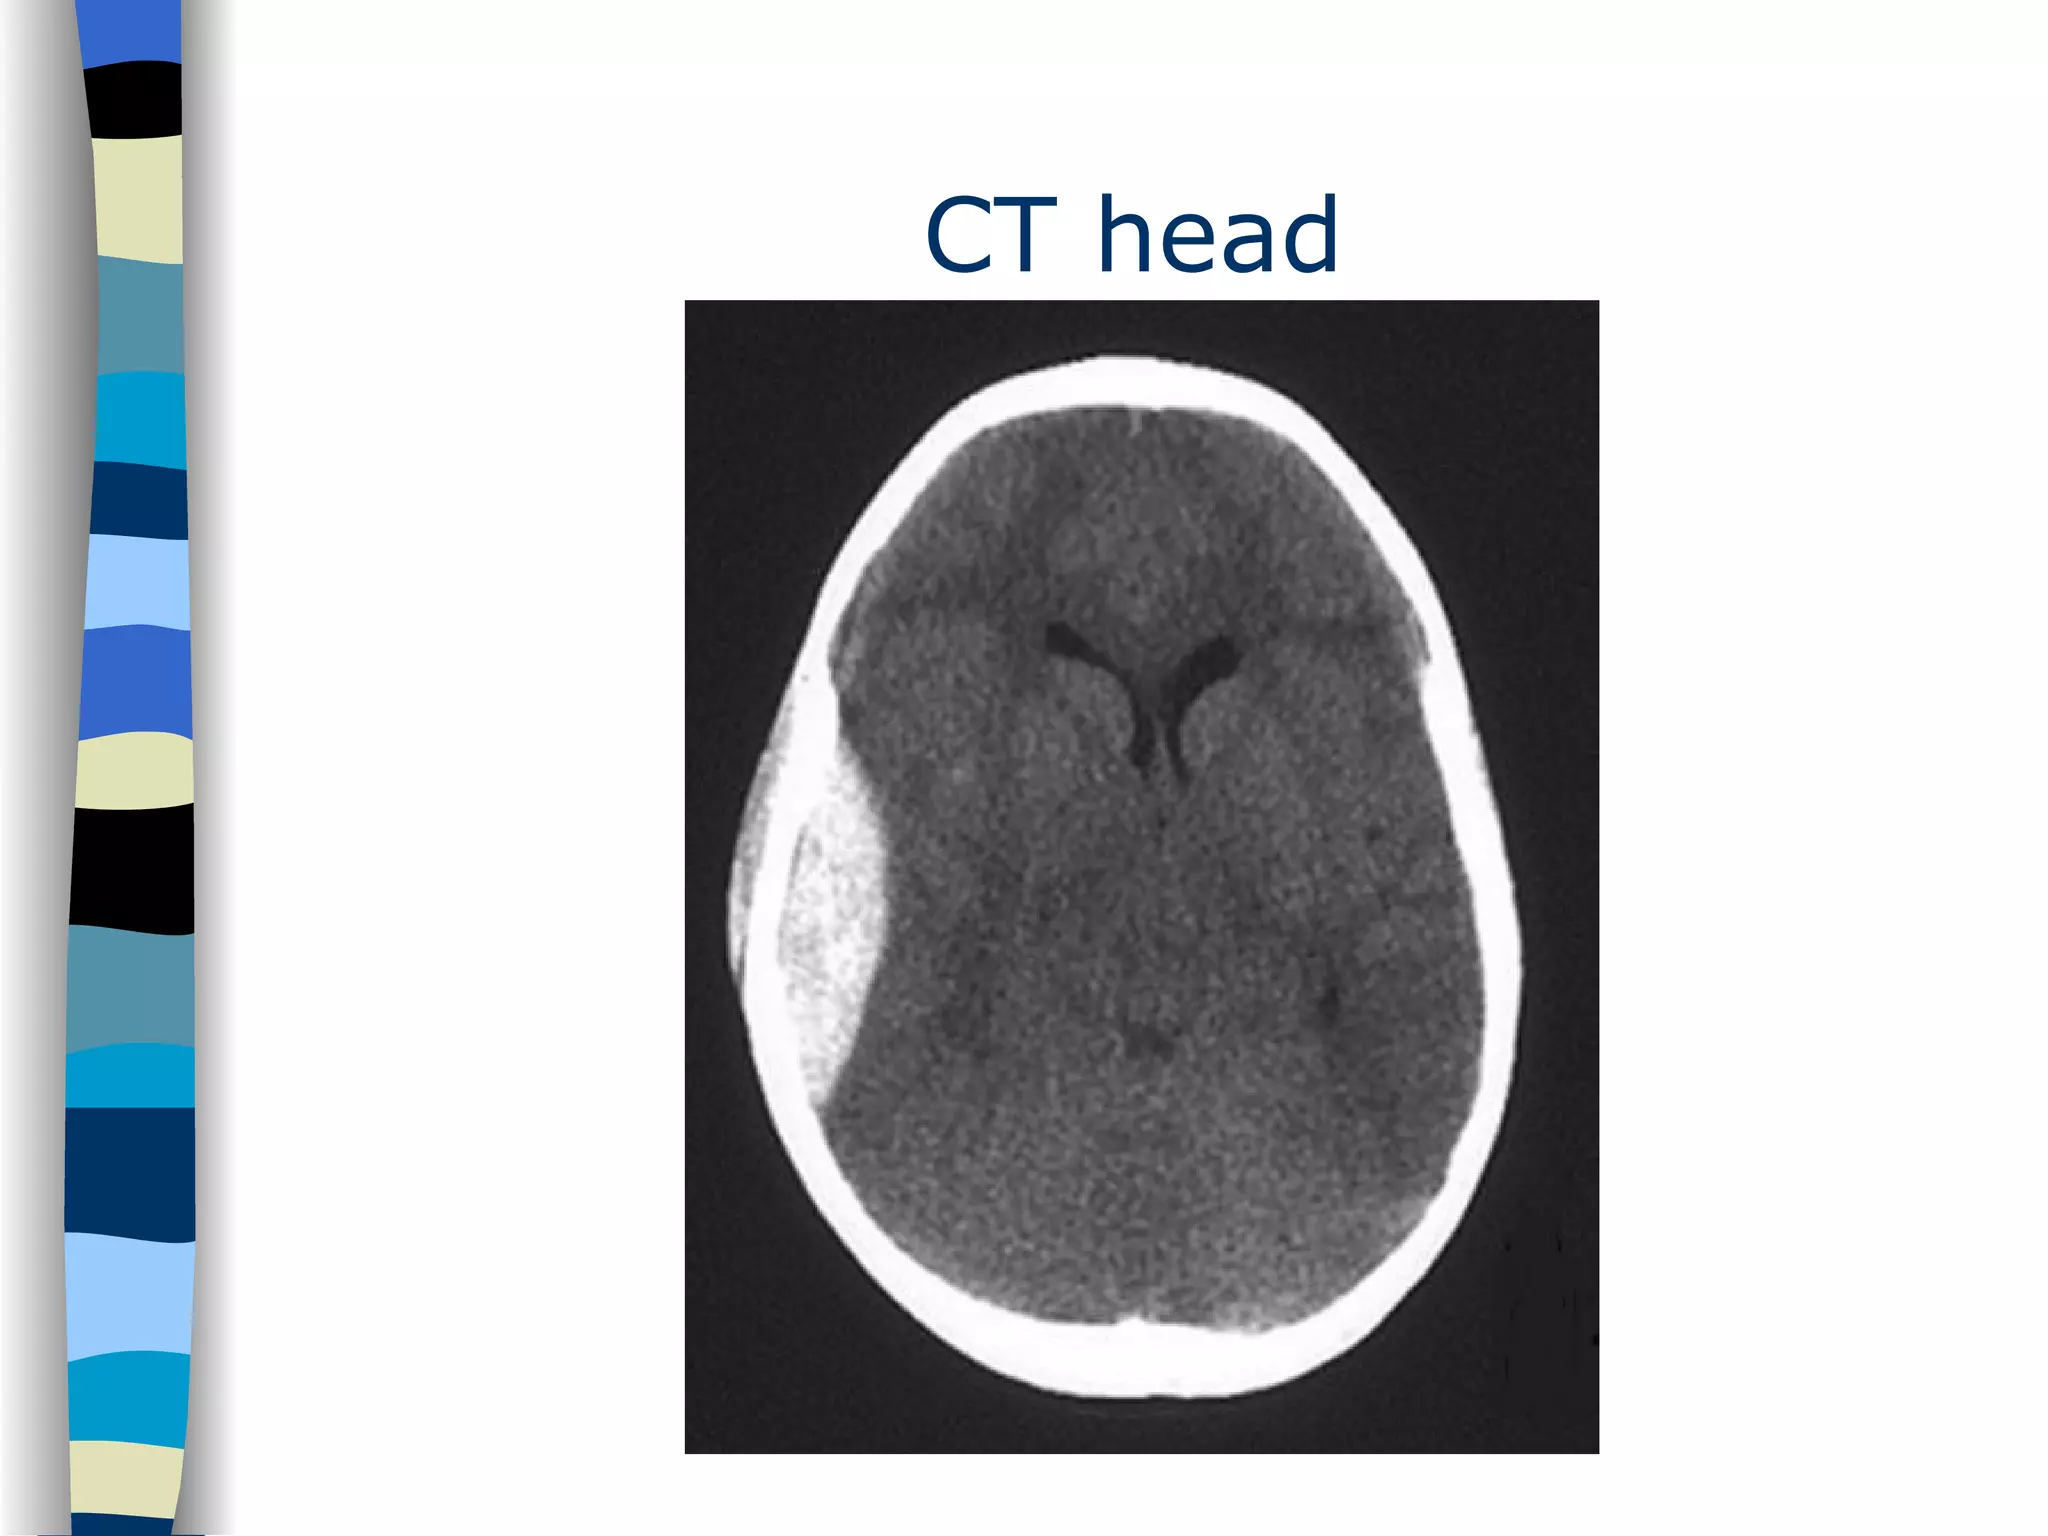

In the meantime… While waiting for the X- ray of the right knee patient starts to vomit. She also complaints of enormous headache. What will you do now?

Head X- ray CT 10

CT head